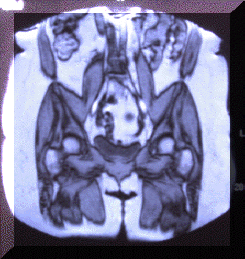

Figure 18. Above is a coronal MRI of the pelvis and lower back. This illustrates the muscles and how they support the pelvis. Abnormal pull or tension will distort the pelvis which is the foundation o f the spine. We use muscle alignment technique to stabilize the spinal foundation, which strengthens the core.